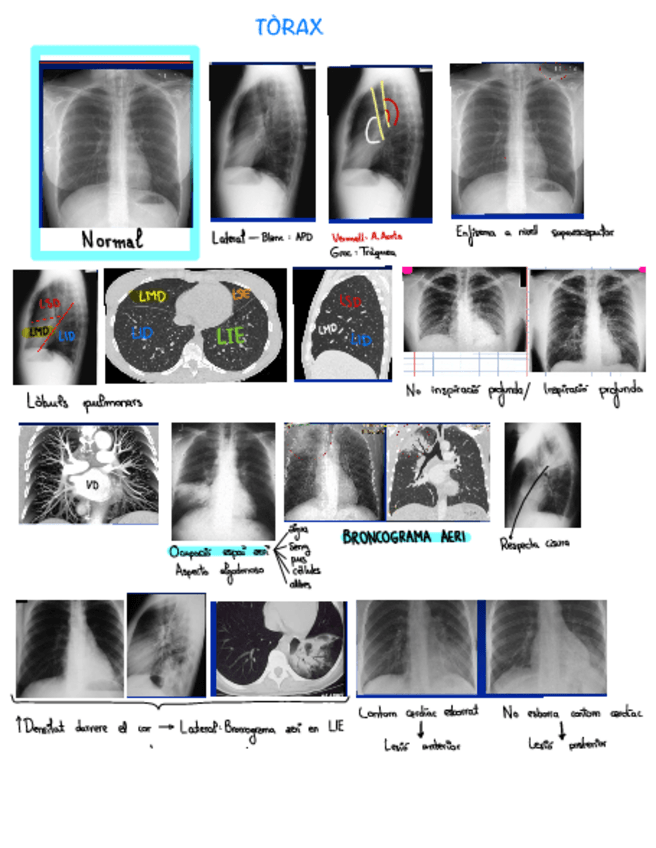

Tema-1.-Torax.pdf

Torax-3.pdf

Torax-4.pdf

Torax-2.pdf

Torax-1.pdf

He publicado nuevos apuntes de 3º ESTUDIO POR LA IMAGEN: torax-todos-los-temas.pdf

He publicado nuevos apuntes de 3º ESTUDIO POR LA IMAGEN: Radiologia-de-torax.pdf